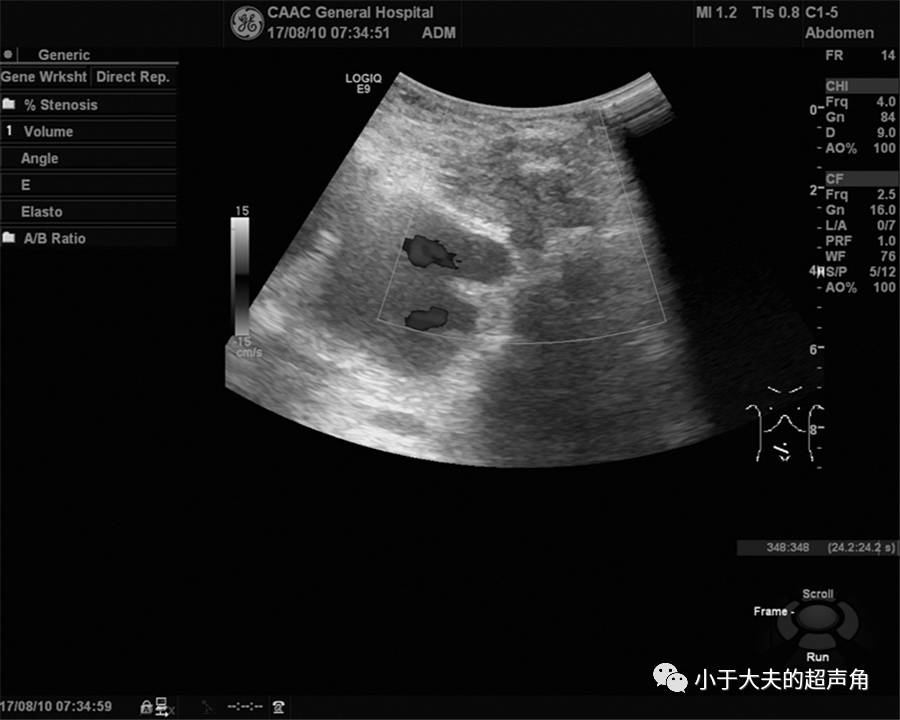

上图:检查时,发现多处肠管扩张,较宽处4.1cm,考虑存在梗阻。在梗阻肠管远端及周边仔细探查,以期发现更多异常之处。